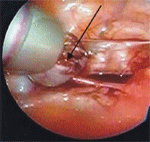

След създаване на пневмоперитонеум до 12 mmHg се въвеждат 3 троакара – един умбиликален от 10 mm за оптиката и два супрапубични от 5 mm за инструменти. След освобождаване на маточните тръби от срастванията със съседните органи чрез биполярна коагулация на мезосалпинкса и последващото му прерязване се отстранява тръбата в максимална близост до матката. Следва екстирпация на хидросалпинкса през 10 mm троакар .

Напълно отделена от мезосалпинкса маточна тръба

Екстракция на отделената маточна тръба през десет милиметров троакар